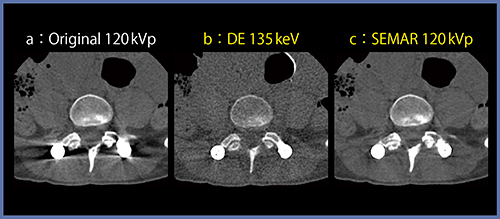

Dual Energy CTの意義の一つに,金属アーチファクト低減(Metal Artifact Reduction:MAR)効果がある。Dual Energyで得られた仮想単色X線画像のうち,高エネルギー側の画像を使用することで,主にビームハードニング由来の金属アーチファクトを低減できる(図5b)。一方,MARについては,Single Energyによる金属アーチファクト低減アルゴリズム“SEMAR”を用いたアプローチも可能であり(図5c),金属やアーチファクトの種類に合わせて最適なMAR手法を用いることが重要となる。

図5 高keV画像とSEMARによる金属アーチファクト低減